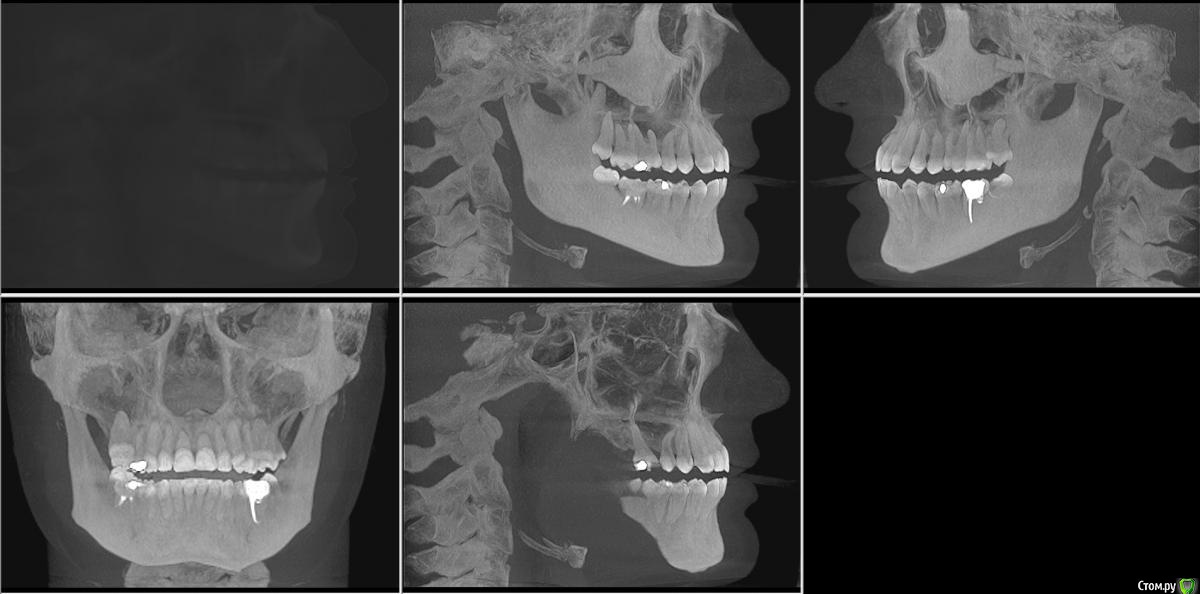

Мне 25 лет. Три месяца назад на НЧ начал расти восьмой зуб с левой стороны. Все проходило без осложнений. Но примерно две недели назад я заметила, что 3 и 4 зубы с той строны начали кривиться. До этого жалоб на прикус никогда не было, зубы были нормальные.

Паралельно с этим два месяца назад было начато лечение 7ого зуба с той же стороны.  Зуб с проблемными каналами в которых, как обнаружилось в ходе лечения, предыдущий врач оставил зацементированый инструмент.  Когда я сообщила доктору о проблеме с искривлением, был назначен прием с присутствием ортодонта.

Стоматолог предлагал вариант удаления проблемной мертвой 7ки и вытягивание на его место 8ки(она здорова и в хорошем состоянии, из десны торчит половинка), но ортодонт категорично ответила, что это невозможно.

Вердикт ортодонта - имеется легкая скученность спереди, удалить обе 8ки на НЧ, на 7ку керамическая коронка и ровнять брекетами.

К сожалению снимков до искривления нет. Но есть свежая 3D комп.томография I-CAT.  Приложу любые нужные ракурсы.